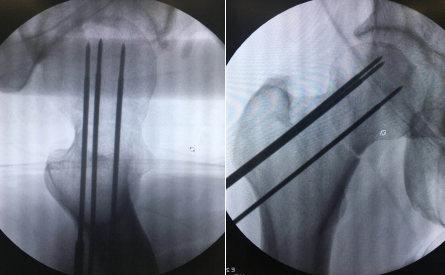

上午10时许,手术团队的新“同事”——“天玑”骨科机器人准备就绪,手术正式开始。10多分钟后,手术团队将形如“天线”的示踪器安装在患者手术处,使用机器人透视下取得股骨颈图像,在电脑上规划空心钉方向,规划完成后由机器人进行精准定位,沿定位套筒置入克氏针固定,透视见克氏针位置及长短适中,依次置入3枚股骨颈空心螺钉固定,再次行C型臂透视正侧位见骨折对位对线良好,螺钉位置以及长短均适中,经过1小时20分钟,机器人手术顺利结束。

“天玑”的秘密在于它拥有强大的光学追踪系统和机械臂。追踪系统可以进行三维透视扫描,能看到人眼看不到的地方,还可以实时监控手术每一个环节;机械臂运动灵活、操作稳定,精准度可达到0.2毫米。